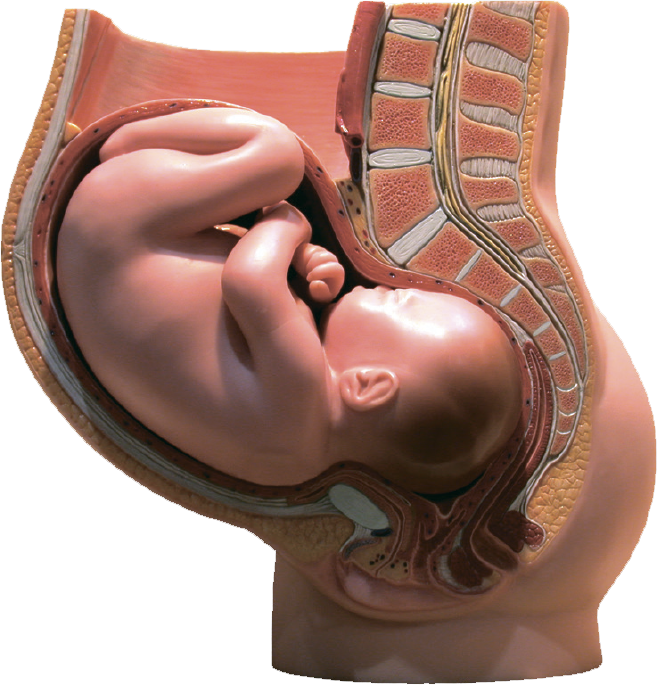

Анатомия женского организма: строение и функции матки